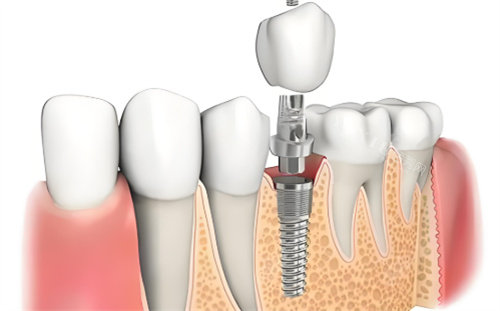

赛迪克CDIC种植牙作为国产种植体的代表之一,在口腔种植领域已经积累了相当的临床经验。其质量表现可以从多个角度进行分析,以下将从技术背景、产品特点、临床应用及性价比等方面展开探讨。

产品特点

CDIC种植体在设计上考虑了多方面的临床需求。其表面处理采用SLA技术,形成有利于骨结合的微观结构。锥状主体和渐变双螺纹的设计使植入过程更为顺畅,同时增强了稳定性。连接方式采用复合设计,有效降低了种植体周围组织发生问题的可能性。

临床应用与结果

从临床应用数据来看,CDIC种植体已经在国境内范围内得到广泛使用。累计使用量较大,覆盖了多种临床场景。对于不同骨质条件的患者,该种植体都表现出了较好的适应性。在即刻种植等复杂病例中,也积累了相当数量的成功病例。